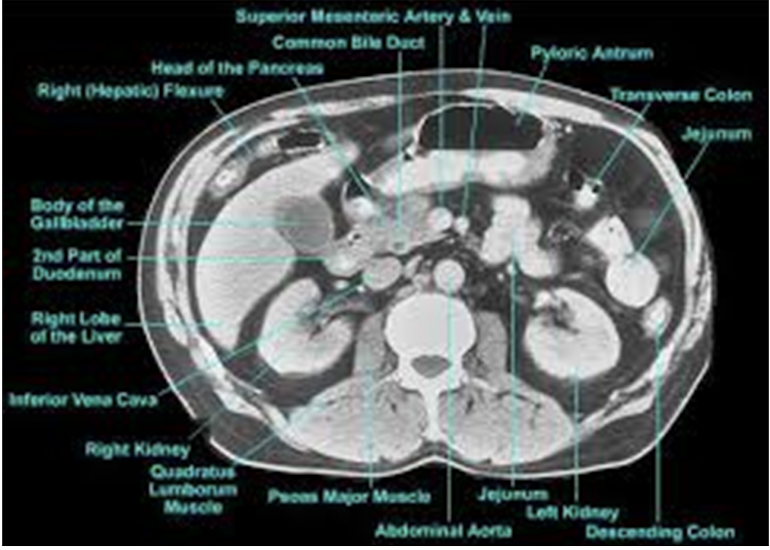

Identify the parts of the GI tract with CT imaging